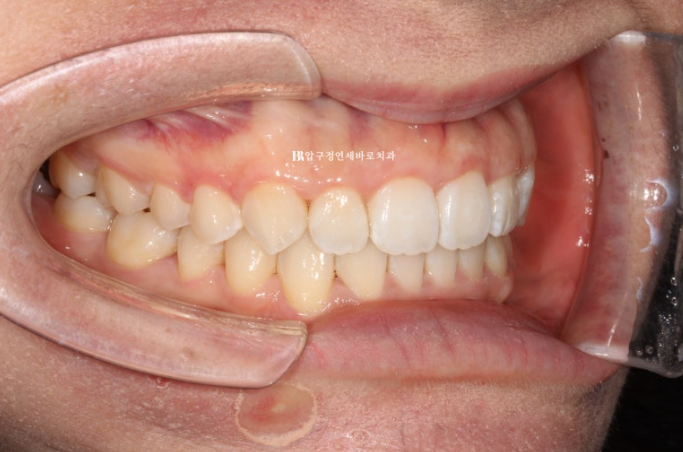

24.04

추가장치 14개를 4개월에 걸쳐 다 낀 후 모습입니다.

중심선이 맞아지고

송곳니 반대교합이 완벽하게 개선되었습니다.

돌출되어 뻗쳐있던 앞니 각도가 개선이 되면서 돌출감이 개선되었습니다.